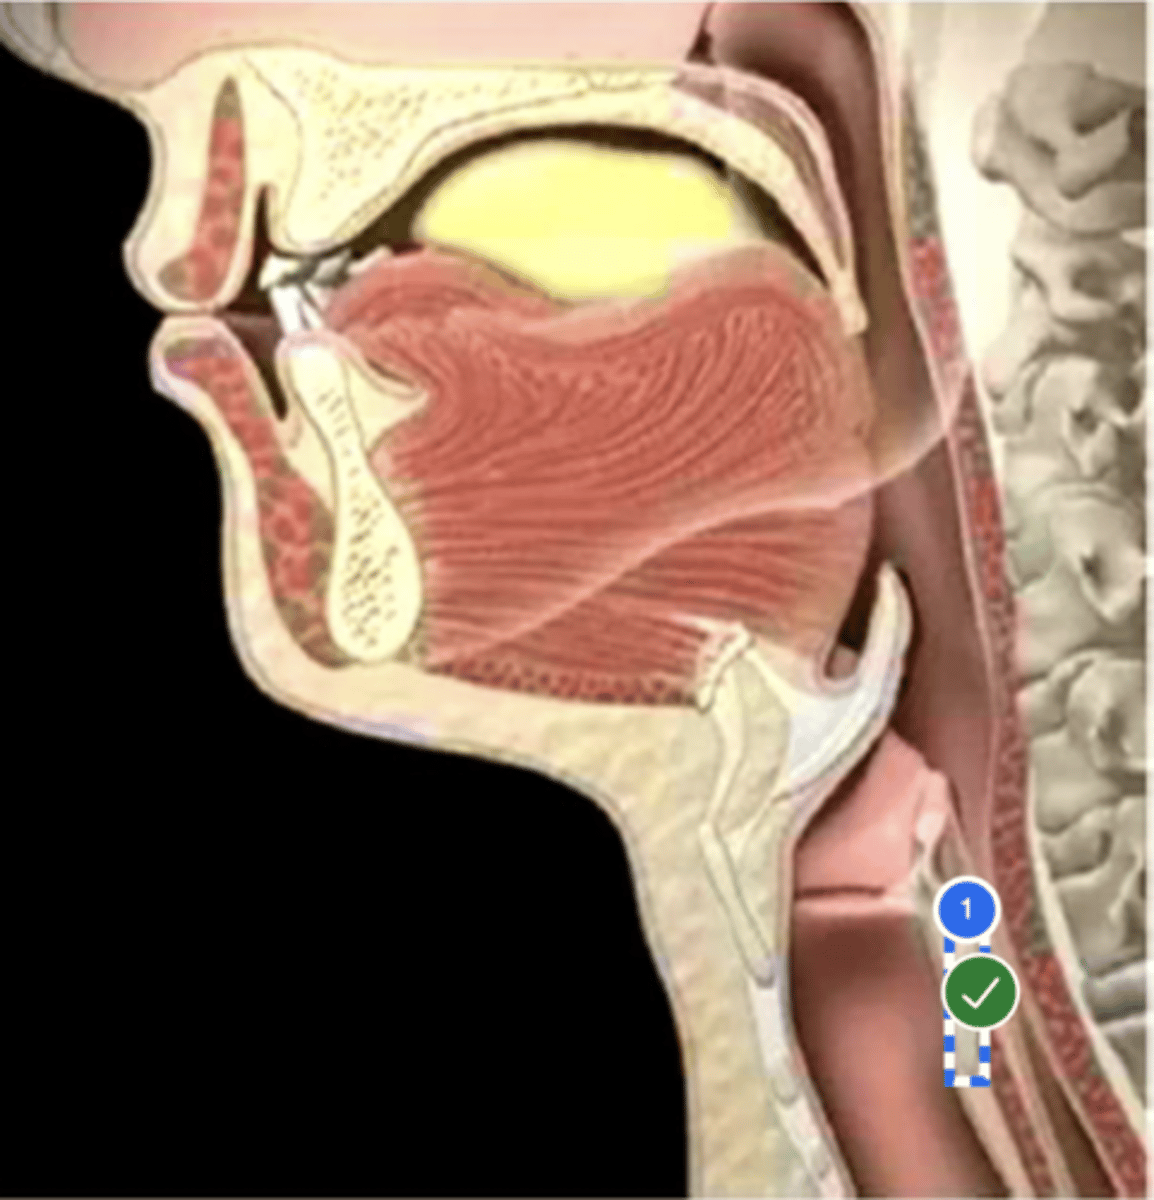

Label Nasopharynx (lateral view)

Label Nasal cavity (lateral view)

Label oropharynx (lateral view)

Label hypopharynx/ hylolarynx

Label tongue (lateral view)

Label soft velum/ palate (lateral view)

Label hard palate (lateral view)

Label mandible (lateral view)

Label base of tongue (lateral view)

label hyoid bone (lateral view)

Label epiglottis (lateral view)

label Line of true vocal folds (lateral view)

label Thyroid cartilage (anteriorly) (lateral view)

Label posterior cricoid (lateral view)

Label esophagus (lateral view)